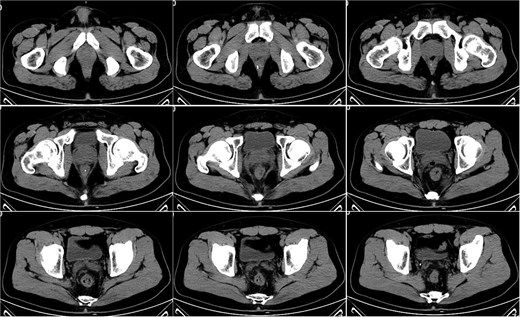

On postoperative Day 7, the patient developed a fever (38.5°C) and mild lower abdominal discomfort. Laboratory tests revealed leukocytosis (white blood cell count: 16.06 × 109/l, neutrophil percentage: 89.1%). A pelvic computed tomography (CT) scan suggested cystitis (Fig. 1). Anti-infective therapy with intravenous cefoperazone sodium and sulbactam sodium was initiated. The patient’s vital signs, complete blood count, and temperature were closely monitored.